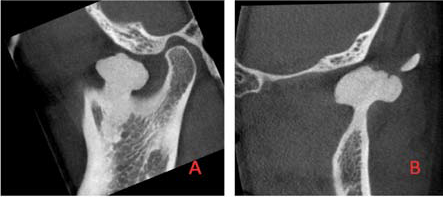

A 42-year-old female was referred to the Oral and Maxillofacial surgery clinic, complaining of a constant ‘contraction’ like movement of her jaw over a one-year period. She was also experiencing preauricular pain in the left temporo-mandibular joint (TMJ) region.She did not report any previous trauma.Clinical examination revealed no swelling or facial asymmetry therefore a full Orthopantomograph (OPG) radiograph was requested to assess for likely sources of the patient’s presenting complaints, which were expected to be a TMJ related disorder or dental pathology. However the radiograph revealed a radiopaque mass related to the left mandibular notch, which was not palpable clinically (Figure 1). A cone beam computed tomography (CBCT) scan reported an 18 x 13 x 14 mm bony mass arising from the left mandibular notch (Figure 2). The lesion had a pedunculated shape with a lobulated outline (Figure 3). The appearance of dense bone suggested an osteoma. Due to the radiographic appearance and peripheral nature of the lesion, the two main differential diagnoses established were a peripheral osteoma or an exostosis. Both lesions have similar histological appearances and therefore need to be differentiated clinically. Unlike the lesion in this case, exostoses are not usually solitary. In addition, lesions stop growing after puberty and are commonly related to areas of attached gingivae.By contrast, peripheral osteomas present as solitary, usually asymptomatic masses of long duration. Radiographically lesions are well circumscribed, oval and have a similar density to the surrounding bone. Histological investigation will be needed to confirm the type of osteoma present i.e. compact, cancellous, or mixed. However, peduncluated osteomas are usually cancellous in nature [5].